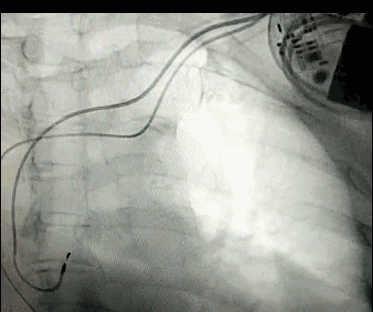

DSA是將造影劑注入需要檢查的血管中,使血管顯露原形,然后通過系統(tǒng)處理,使血管顯示更加清晰,便于醫(yī)生診斷或進(jìn)行手術(shù)。

數(shù)字減影血管造影術(shù)是醫(yī)學(xué)影象學(xué)中,繼X線CT之后的又一項(xiàng)新技術(shù),也是當(dāng)前醫(yī)學(xué)影象學(xué)中具有突破性的重大進(jìn)展。?